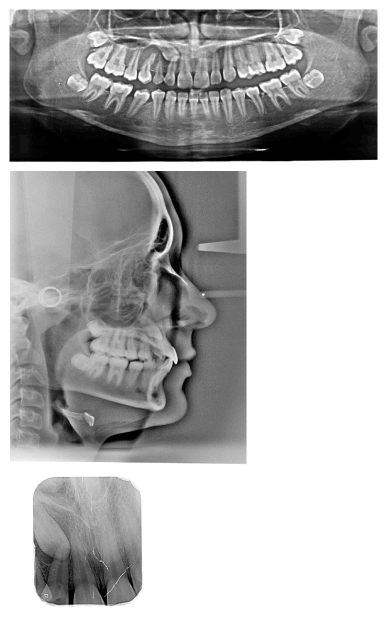

0.022 slot Roth brackets had been bonded on all upper and lower teeth except #12 which acted as a free body initially till the canine had been moved away from its root (Figure 3). After 6 months of alignment, space started to be created for the canine using opening coil spring (0.010 x 0.035 inch) (Figure 4). The first stage of surgery was planned to be VISTA technique in order to move the canine horizontally and to situate the canine crown directly under its socket using the microimplant (MI) (Figures 5 and 6). During surgery, all the bone distal to the canine crown till its CEJ which is in the way of its movement had been removed. A microimplant from (Ormco) VectorTas of 2 x 8 mm had been placed in the infrazygomatic crest parallel to the upper right first molar (Figure 7). A lingual button bonded on the labial surface of the canine and connected to the microimplant via a power chain which was passing under the alveolar mucosa over the canine. The horizontal movement of the crown had been activated every month by cutting a hole from the power chain. A panoramic periapical radiograph A-B taken directly after MI placement and 3 months over that to control the movement of the canine (Figures 8 and 9). After 3 months of horizontal movement of the canine, the patient referred again for the 2nd stage of surgery where a full reflected flap performed in order to remove the old power chain and place new one which is directly connected to the main archwire (Figure 10). All the bone above the canine crown till the 2 mm from the alveolar crest had been removed in order to facilitate the tooth movement vertically. The main arch wire which is 0.017x0.025 Stst had been offset in the area between #12, 14 (Figure 11). This offset placed to help for keeping the canine root in the alveolar bone and avoid the labial tipping of the crown. A crimpable attachment with a hook fixed on the wire directly over the canine crown and a power chain connected directly from the lingual button to the hook (Figure 12). The vertical movement of the crown had been activated every month by cutting a hole from the power chain. After the canine came out of the soft tissue a bracket bonded and thin wire placed in its slot with a sequence of 0.12 Niti, 0.14 Niti, 0.16 Niti, 0.16 x 0.22 Niti, 0.16 x 0.22 Stst, 0.17 x 0.25 Niti and 0.17 x 0.25 Stst. Canine root torque had been checked after its reaching to the occlusal plane and found that no need for any adjustment since it is similar with the opposing canine root eminence (Figure 13). After 24 months of active treatment, all appliances were debonded (Figure 14). Orthopantogram, lateral cephalography and periapical radiograph had been taken to record as a baseline for future follow up and assessment. Clear overlays delivered for both arches as retainers with proper instructions (Figure 15).

Figure 5. Photos show the placement of microimpant in the region of #16 and using power chain to move #13 distally in the horizontal plane

Figure 6. A schematic drawing of the recently developed VISTA technique (Vertical Incision Subperiosteal Tunnel Access), a minimally technique, combined with bone screws which is indicated in labially impacted cuspids

Figure 7. A panoramic radiograph shows the insertion of the micro implant and the button which had been to the labial surface of #13

Figure 8. A panoramic radiograph 3 months past traction #13

Figure 9. A- Intra oral radiograph immediately before horizontal movement of #13; B-3 months post traction #13